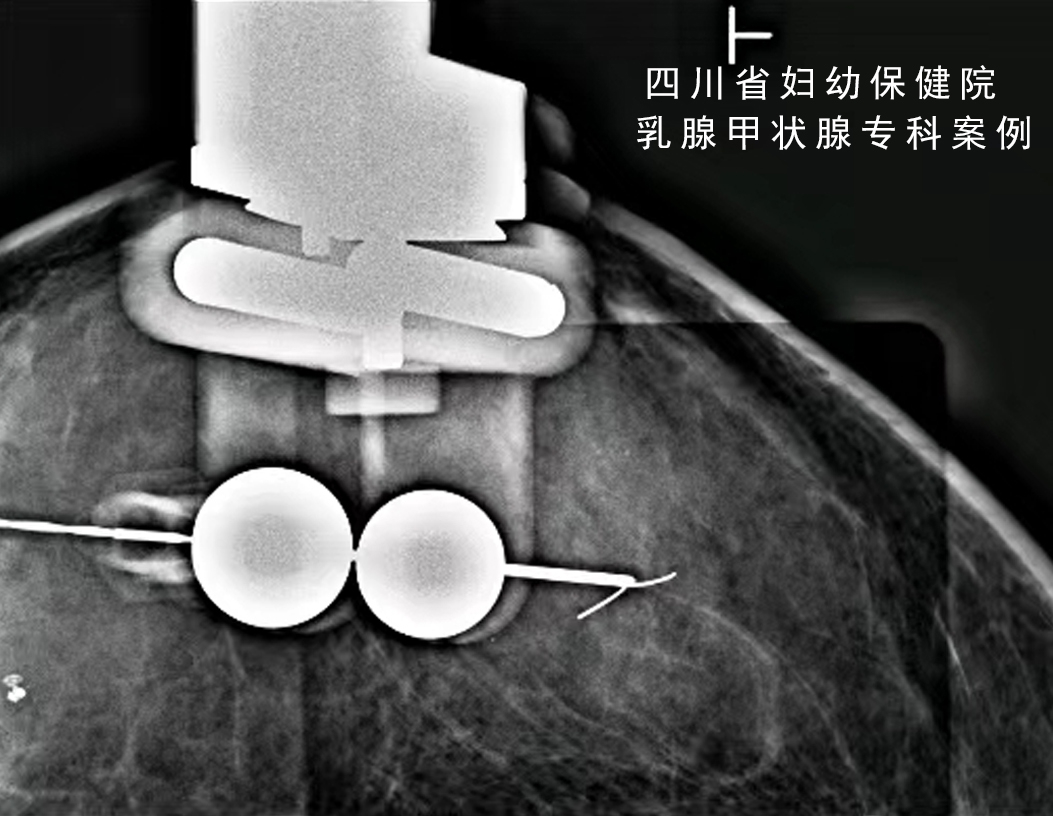

大致过程是,在其中一种体位下,将一次性的无菌定位钩针垂直插入病灶处。再变换体位,确定在另外一个平面上是不是也在病灶里。

通过两个平面的确认,保证三维立体定位的精准。手术中,临床医生通过寻找定位钩针,沿着钩针附近切除,可以在保证切除病灶的同时,减小切除范围。

这样的技术优点是比单纯的体表定位相对准确,但患者需要先在局麻下做一次定位,然后再做一次开放切除手术,且需要反复多次加压乳房曝光,造成乳房压迫不适。

怎么制造手术钩针看医生如何精准“钩出”乳腺钙化灶,将早期乳腺癌“绳之以法”_https://www.jmylbn.com_新闻资讯_第3张

(在侧位,将定位针垂直插入钙化灶附近)